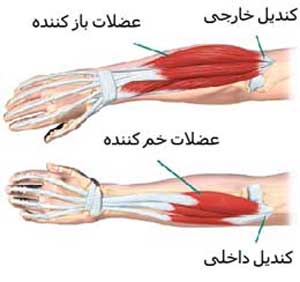

کشیدگی ماهیچهها و رگ به رگ شدن

زمانی که اقدام به یک تمرین بسیار سریع و شدتی میکنید به دلیل شوکی که به عضلات وارد میکنید اگر عضلات شما آمادگی نداشته باشند ممکن است دچار کشیدگی بیشازحد بافتهای ماهیچهای شوید؛ بنابراین سعی کنید همواره بدن خود را گرم کرده و روی تمرینات انعطافپذیری تمرکز کنید.